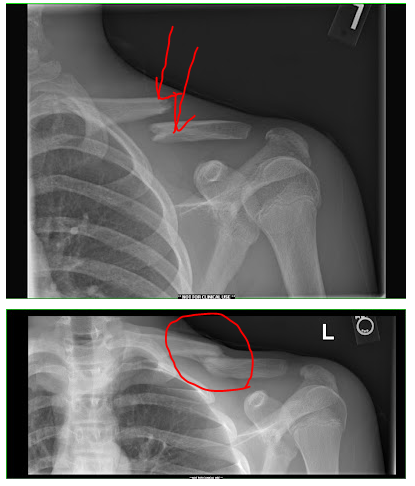

겉으로 보이는 소견으로는 위 사진의 빨간 화살표처럼 쇄골 중심 부위가 솟아오르거나 붓는 증상이 많습니다.

진단에서 가장 중요한 것은 x-ray 방사선 사진입니다.

x-ray상에서는 다음과 같은 모습을 보이게 됩니다

골절이 된 모습을 확인할 수 있고, 얼마나 벌어졌는지, 분쇄(뼈가 으스러짐)은 있는지 등을 확인할 수 있습니다.